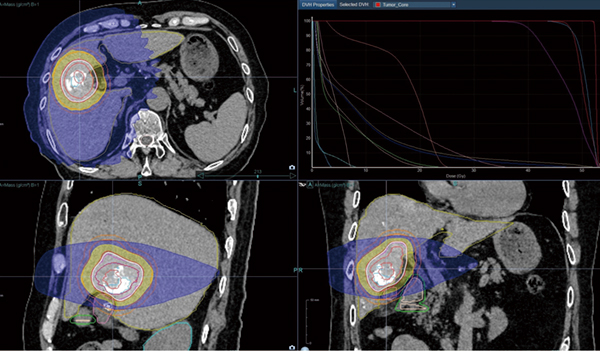

Radixactによる治療例を紹介する。78歳男性,肝細胞がんの診断にて当科で肝動脈化学塞栓術(TACE)を施行した。その後のCT評価で腫瘍中心〜辺縁にリピオドールの沈着不良部があり,TACE後2週目のAFP 9.27ng/mL,PIVKA-II 128.32 mAU/mLで腫瘍遺残が強く疑われ,放射線治療依頼があった。リピオドールの沈着が強く残っている部分があり,TACE後の高吸収を利用したマーカーレスのSynchronyシミュレーションを行い,標的認識に問題がないことを確認し,PTV D95 40Gy/4fr処方でSRTを施行した。線量分布図を図3に示す。SRT3か月後の造影CTにてがん遺残部の増強効果は低下し,AFP 4.39ng/mL,PIVKA-II 22.81mAU/mLに正常化し,有害事象もなく良好な経過を確認している。肝腫瘍においてリピオドールなどの高吸収が存在し,マーカーレスのSynchronyによる動体追尾照射が可能であった貴重な症例であった。

図3 TACE後リピオドールを利用したSynchrony(マーカーレス)のSRT

治療計画は単純および造影CTによるCT/CT fusionで実施した。